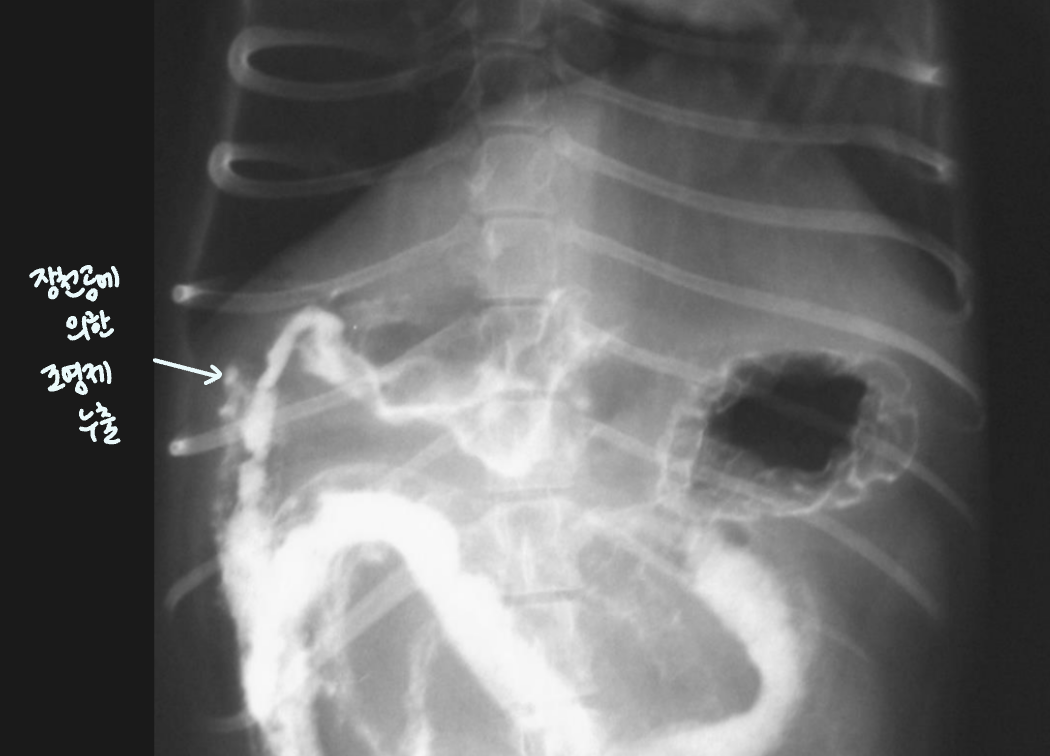

Intestinal perforation (์ฅ์ฒ๊ณต)

- ๋ฐ์ด, ๊ตฌํ , ๊ธฐ๋ ฅ์ ํ, depression ๋ฑ์ผ๋ก ๋ด์, 1์ฃผ ์ ๊ต์ history.

- ์ฅ์ฒ๊ณต โ ๋ด์ฉ๋ฌผ ๋น ์ ธ๋์ด โ ๋ณต๋ง์ผ์ผ๋ก ์งํํ ๊ฒ. (1์ฃผ์ผ์ด๋ฉด ๋ณต๋ง์ผ์ผ๋ก ์งํํ๊ธฐ ์ถฉ๋ถ!)

- ๋ฐฉ์ฌ์ ์ serosal detail ์ ํ (๋งค์ฐ ์ฌํ ์ผ์ฆ), ๋ณต๊ฐ ๋ด ์ ๋ฆฌ gas ๋ง์.

- ์ด๋ฌผ, ๊ต์, ์ฐฝ์์ ์ํด ์์๋ ์ ์์.

- ๊ถค์ โ Saw-like ulcer lesion, ๋ด๊ฐ์ด ์ง์ ๋ถํจ

- ์กฐ์์ ๋์ถ ๊ด์ฐฐ๋จ.

| ๋ณต๊ฐ ๋ด ์ ๋ฆฌ gas | saw-like ulcer lesion | ์กฐ์์ ๋์ถ |